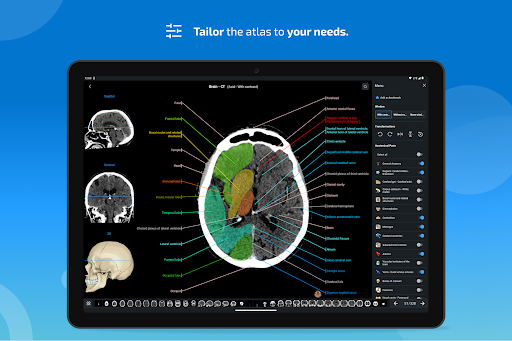

- يمكنك الآن استخدام قائمة الإعدادات والتمرير عبر الصور في نفس الوقت على الأجهزة اللوحية

جديد: يمكنك الآن تصفية الوحدات حسب المنطقة أو نوع المحتوى حتى تتمكن من العثور على الوحدة التي تبحث عنها بشكل أسرع.